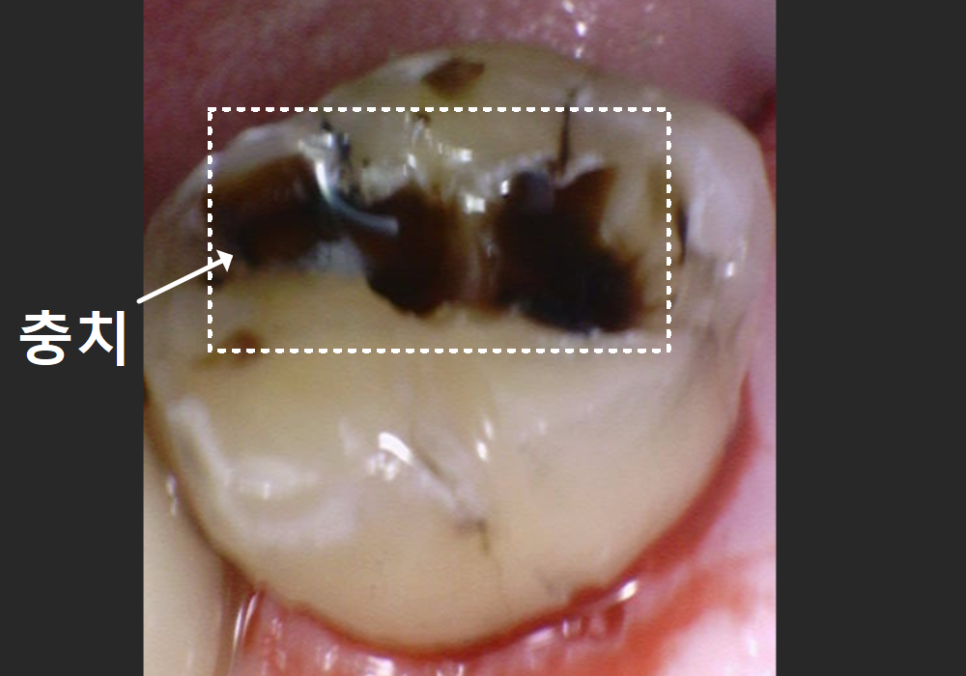

조심스럽게 빠진 자리를 살펴보니,

역시나 치아 내부에

까맣게 충치가 진행되어 있었죠.

250822

하지만..

엑스레이와 구강 상태를 꼼꼼히 확인해 보니,

이번 치아는 다행히

발치 없이 충분히 살려서 쓸 수 있는 상태였습니다.

이번 케이스가 지난번과 달랐던 결정적인 차이,

바로 금니 표면의 '구멍' 유무였습니다.